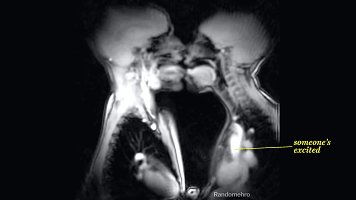

从下图可以看出两个人的舌头

都开始不老实了,接吻会加剧兴奋

会使心跳速度进一步增加

呼吸也会更急促,全身的肌肉

开始出现不规则的收缩肌紧张